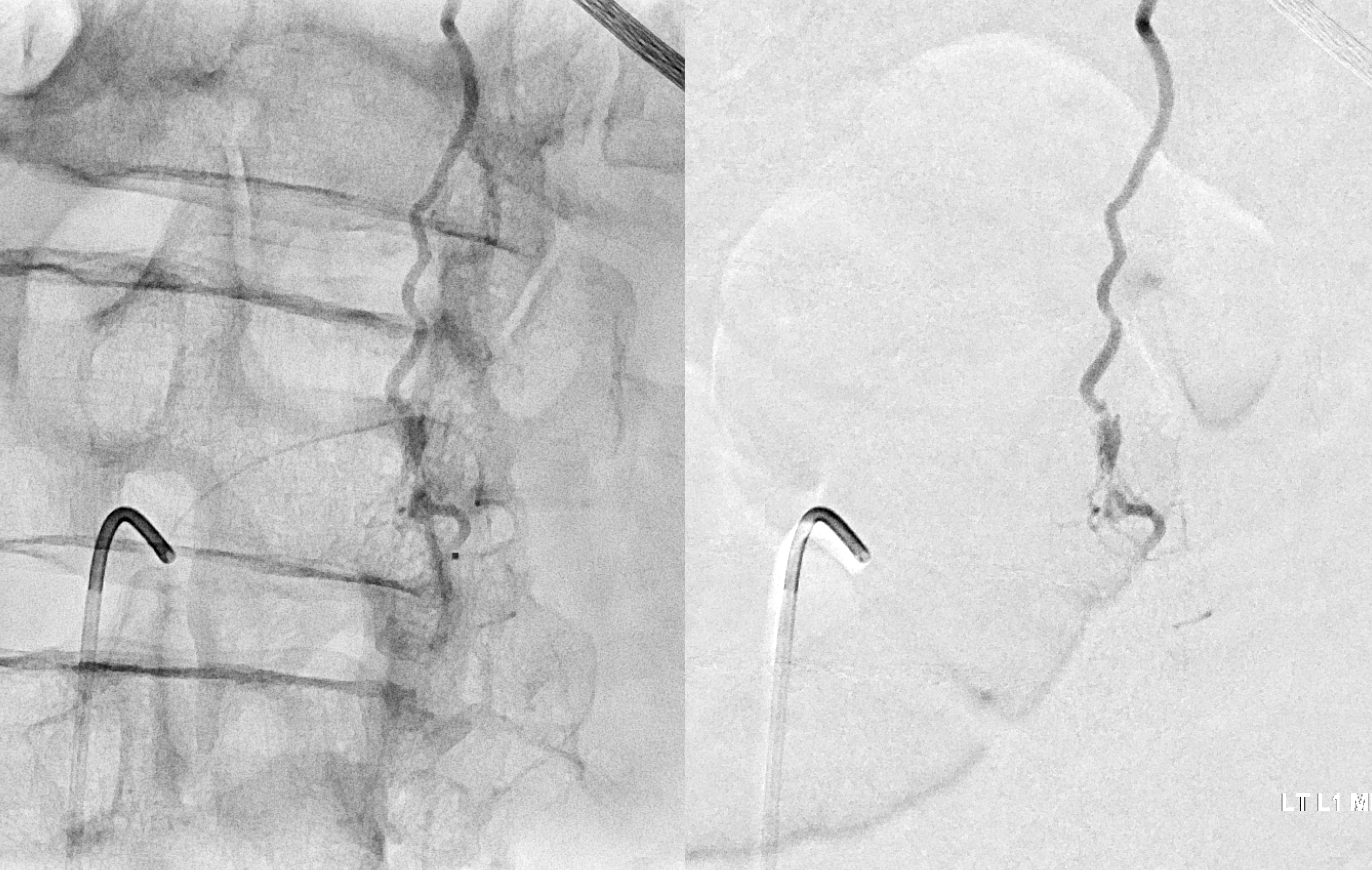

Fistula at left L1

All dural fistula pathophysiology, and spinal too, consists of two key factors. One is fistula. The other is degree of venous congestion. Normal spinal venous anatomy consists of multiple radicular veins which drain the cord via nerve root sleeve / foramen into the epidural venous plexus. These veins are almost always deficient (missing from getgo, thrombosed, both?) in patients with spinal dural fistulas. Could it be that venous deficiency comes first, and fistula emerges later? Probably not, but interesting to consider. In any case, good spinal angiography involves imaging of fistula runoff to see extent of congestion and where drainage finally happens. In this case, there are no radicular veins in lumbar or thoracic cord at all. Not until the foramen magnum/C1/C2 do we see any outflow, and that is insufficient as well — with congestion extending all the way up to basal vein! Note perfect visualization of anterior pontomesencephalic and interpeduncular veins. When it finally reaches basal vein, the outflow is diluted by cranial venous tributaries.

In retrospect, corresponding veins on MRI and angio

Very important to find both dominant radiculomedullary supply to the lower cord (aka Adamkiewicz) and posterior spinal arteries. In the Adamkiewicz injection, there is usually no venous phase due to fistula-related congestion. In this case, not only we dont see veins, we also don’t see the conus basket. That is frequently seen from posterior spinals, except in this case we did not see posterior spinals either. That is a concern since we don’t want to inadvertently embolize them. However, given the congestion the most likely explanation is that the basket normally opacifies from the Adamkiewicz / ASA, and is congested by fistula.